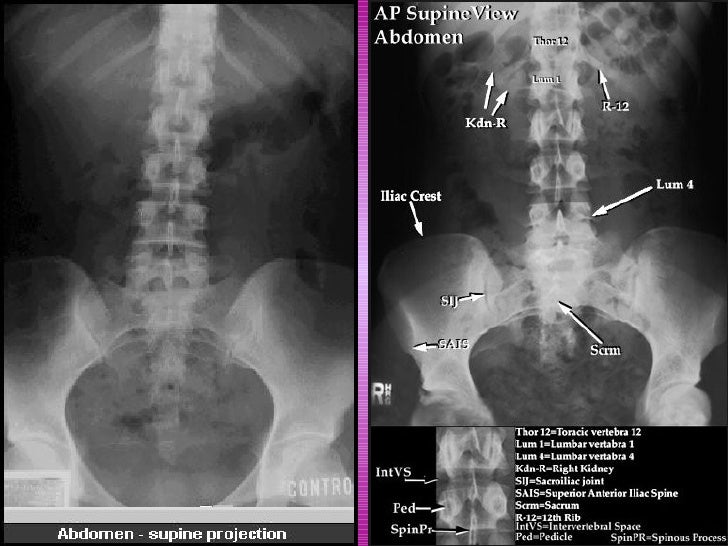

Home » abdomen

45+ Radyolojik Anatomi Abdomen